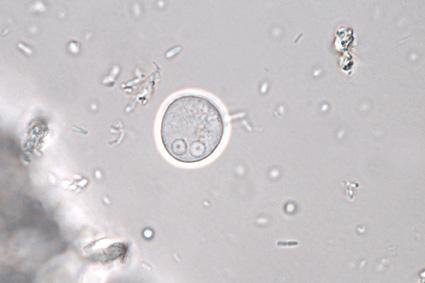

10. Completely identify the name and stage of the parasite. Wrong spelling is wrong. Incomplete answers will be incorrect as well. (e.g. Entamoeba coli cyst)

The correct answer is Entamoeba coli cyst. The question asks for the complete identification of the name and stage of the parasite, and the answer provided fulfills this requirement. Entamoeba coli is a species of amoeba that can be found in the human intestine. The cyst stage is the dormant form of the parasite, which allows it to survive outside the host and be transmitted to new hosts.